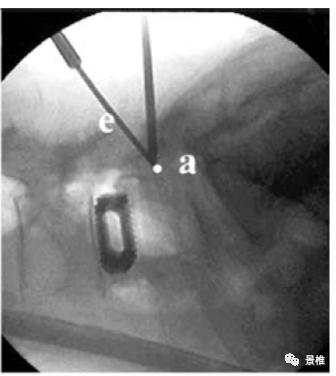

进针点位于棘突根部,指向对侧横突中点与椎弓根外缘交界处。

术中C臂透视正侧位所指向的关键点。

腰椎椎板板障厚度足够,可置入直径4.5mm的螺钉,穿透4层皮质钉住一侧关节突关节。双侧固定生物力学强度足够。